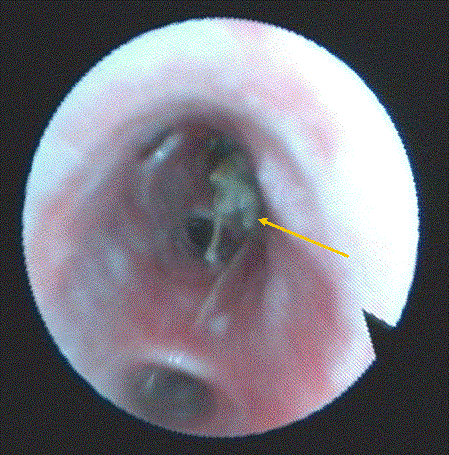

Fig 1

Bronchial Foreign Body